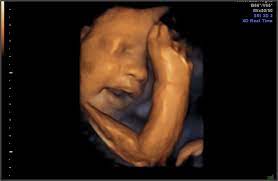

At this stage, the baby has put on some weight and filled out to make features more visible, yet still enough fluid in front of baby's face to obtain great images. I'm only at 31 weeks, but i had that 4d/3d u/s and yes, baby looked totally deformed. We just went yesterday at 31 weeks 4 days. In fact, it's quite similar to 4d ultrasound. Up to 32 weeks there generally still room for the baby to move. View images & learn more 30 week ultrasound The 4d ultrasound uses sound waves to create this moving image. Sofort kostenlos und ohne anmeldung anfragen

It is a fun time for the ultrasound as many times you will see movements like smiling, eyes blinking, hands moving, and many other movements. If you are having multiples this is also a good time to capture 3d pictures of the babies. At this stage, the baby has put on some weight and filled out to make features more visible, yet still enough fluid in front of baby's face to obtain great images. Your baby has to hold very still so that the high frequency sound waves have time to form around your baby's features. Snuggling cord at 18 weeks. The 4d ultrasound uses sound waves to create this moving image. Up to 32 weeks there generally still room for the baby to move. Baby impressions is an elective 3d 4d ultrasound imaging facility. At 18 weeks, your baby has mastered the art of yawning, along with hiccuping, which you may feel soon. You learn today about your baby development, prenatal care (doctor visits) and fetal ultrasound at 31 weeks. I'm only at 31 weeks, but i had that 4d/3d u/s and yes, baby looked totally deformed. Sounds like you have a very active baby! We require that all mothers have documentation of their prenatal care and most recent diagnostic ultrasound.

Come and see for yourlself. The best proof is our gallery of weekly 3d ultrasound images taken from 13 weeks and until up to 39 weeks. This page shows typical 3d ultrasound images from 11 to 36 weeks. All 3d ultrasound photos were taken in greenville sc at baby impressions. 18 week hd live/4d ultrasound. 3d/4d ultrasound march 31, 2021 | by kamrynlea has anyone gotten a 3d/4d ultrasound around 26/27 weeks? (so 31 weeks pregnant is the perfect time!) We do not perform medical ultrasounds. I have one scheduled and want to see some pics of what to expect!! At this stage, the baby has put on some weight and filled out to make features more visible, yet still enough fluid in front of baby's face to obtain great images. You're just dying to know what baby looks like inside your 31 weeks pregnant belly. Yawns, stretches, and even smiles are often captured in our 3d & 4d ultrasounds, and we look forward to sharing this miracle with you as well! Snuggling cord at 18 weeks.